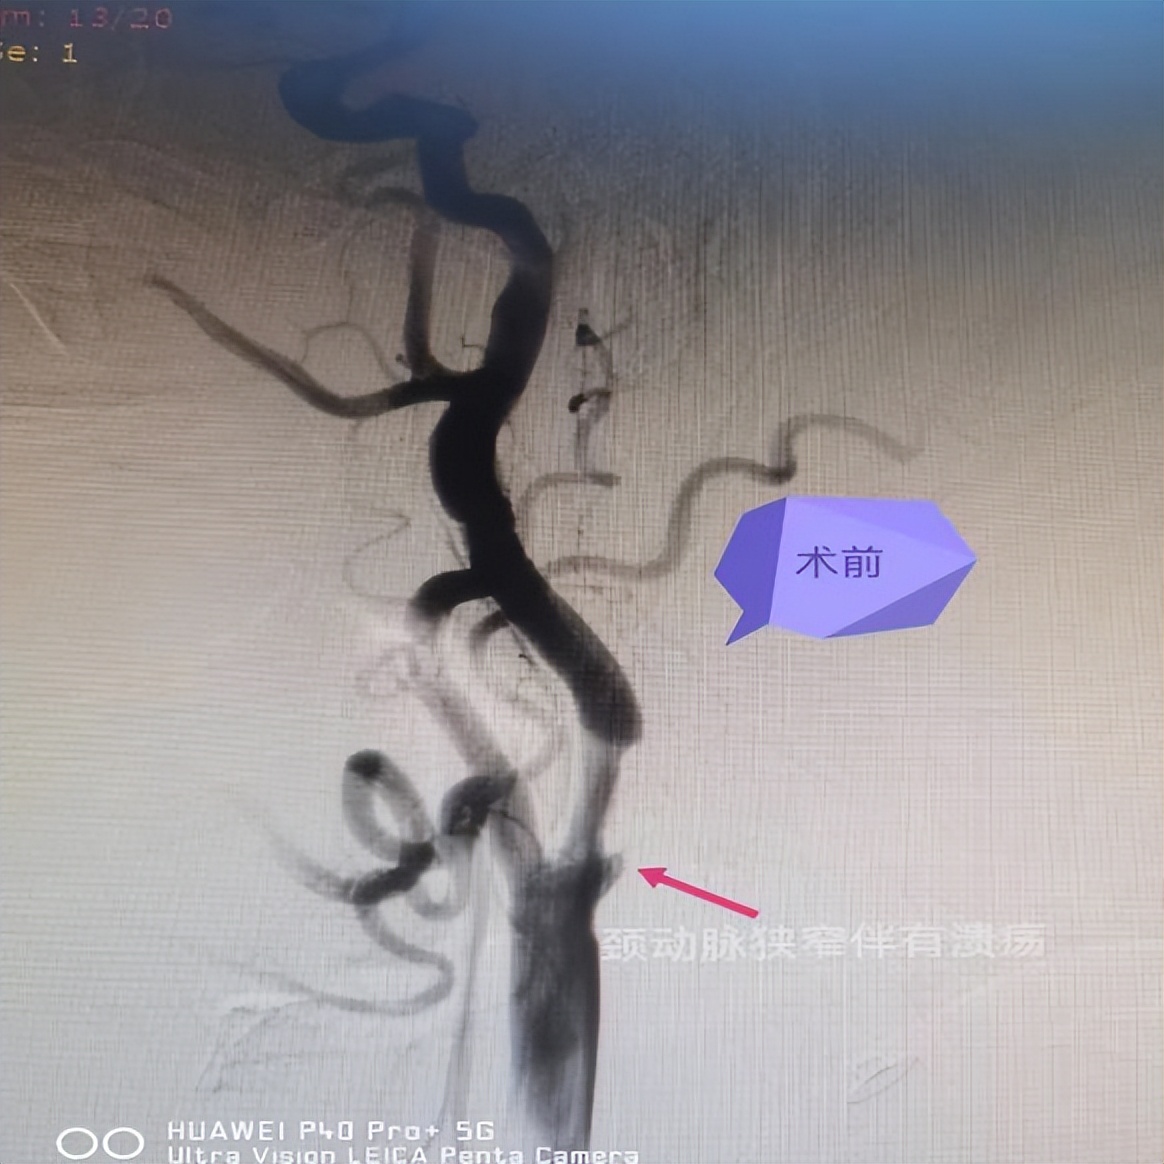

病例二: 右侧颈内动脉起始部位狭窄伴溃疡斑块球囊扩张+支架植入术

患者男性,66岁,以“左侧肢体活动不灵24小时”之主诉入院,入院诊断为急性脑梗死。脑血管造影提示右侧颈内动脉起始部位狭窄(狭窄率约60%)伴溃疡斑块形成,综合评估后在局部浸润麻醉下行右侧颈内动脉起始部位狭窄伴溃疡斑块球囊扩张+支架植入术。手术过程顺利,术后造影见狭窄明显解除,术后患者未诉不适。